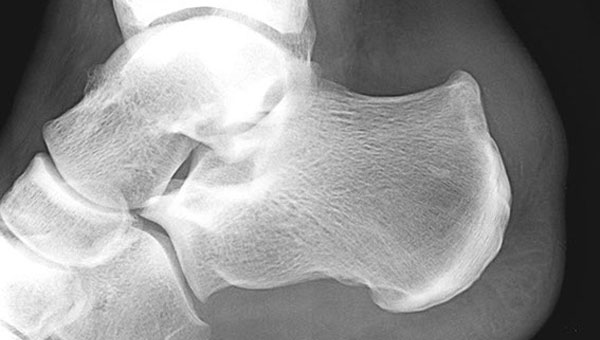

Перед началом терапии необходимо выяснить, является ли шишка на пятке деформацией Хаглунда. Для этого выполняется рентгенологическое исследование, которое позволяет определить, преобладает ли костная структура в образовании. Если результаты окажутся отрицательными, может потребоваться магнитно-резонансная томография. Эта процедура помогает установить природу образования на стопе, так как одной из причин появления нароста может быть наличие жидкости в слизистой сумке.